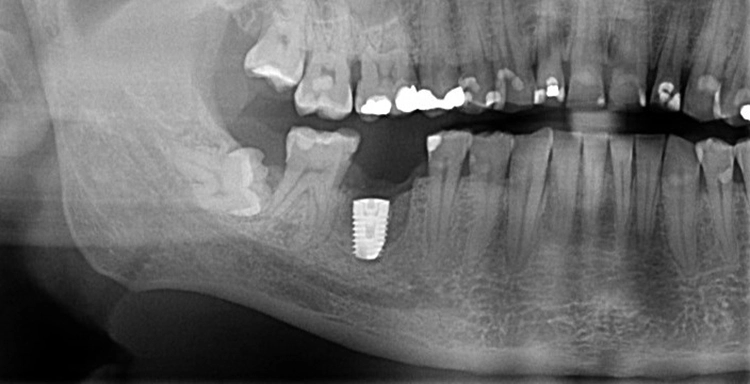

5. Multiple Sofortimplantationen in Zusammenhang mit internem Sinuslift

Beim vorliegenden 54-jährigen Patienten mussten aufgrund von lokaler Parodontitis die Zähne 25, 26 und 27 entfernt werden. Im apikalen Bereich lag jedoch gesunder Kieferknochen vor, sodass eine Sofortimplantation möglich war. Aufgrund der guten Einsichtbarkeit des Operationsgebietes nach Zahnextraktion konnte in diesem Fall flapless vorgegangen werden.

In regio 26 konnte das Implantat dabei komplett apikal im gesunden Knochen verankert werden. In regio 27 jedoch wurde lediglich eine Restknochenhöhe von 8 mm bestimmt. In diesem Fall wurde die Sofortimplantation mit einer internen Sinusbodenelevation nach Summerset kombiniert.